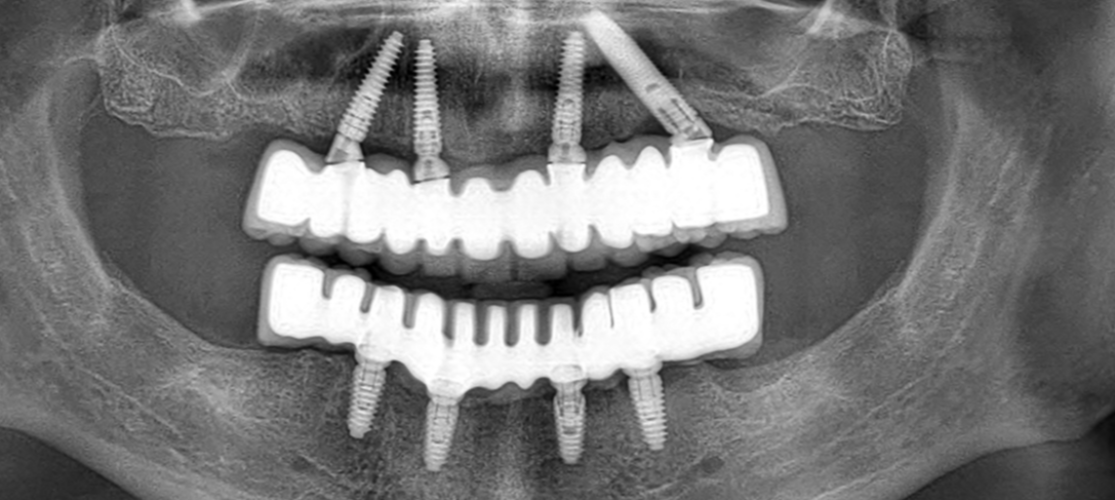

Метод имплантации All on 4 – это современная и технологичная процедура, позволяющая в один и тот же день установить зубной протез на 4 зубных имплантата у пациентов с полной адентией.

В отличие от стандартных методов имплантации, установка имплантатов под разными углами и выбор супраструктуры, соответствующей этим различиям углов, исключает 3-6-месячный период заживления, ожидаемый без зубов, до тех пор, пока протез не будет изготовлен в классической системе имплантатов.

Методика имплантации All on 4  планируется и безопасно применяется к пациенту после проведения клинического и рентгенологического обследования пациента, проведения необходимых измерений с помощью компьютерной томографии. Система имплантатов All on 4— идеальный метод использования фиксированных зубов для пациентов с потерей костной массы задних зубов.

На следующий или один день после установки имплантатов пациенту надевают несъемный временный зубной протез и оставляют имплантаты приживаться вместе с этими временными зубами. После достижения остеоитеграции пациенту устанавливаются постоянные эстетические зубы.

Процедура All on 4 предполагает установку четырех зубных имплантатов в каждую челюсть для поддержки полной зубной дуги протеза. Два имплантата устанавливаются вертикально спереди, а два имплантата – под углом сзади, чтобы обеспечить максимальный контакт с костью.